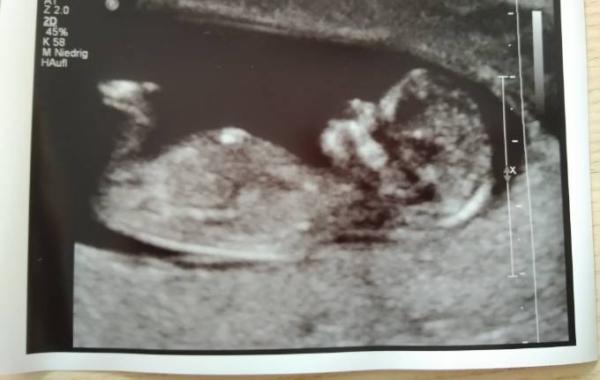

So, heute hatten wir das Erstrrimesterscreening. Es gibt keinerlei Auffälligkeiten und unser Baby ist jetzt 6,1 cm groß. Es war wieder putzmunter und hat es dem Doc nicht immer leicht gemacht, so schnell bewegte es sich. Ein vorsichtiges Outing gab es auch. Laut Chefarzt des Krankenhauses sind wir im Team rosa Ach das wäre echt genial Nächste Woche sollen die Ergebnisse des Bluttests da sein, dann wissen wir es ganz genau. Ich freu mich einfach jedes Mal, dieses kleine Wunder sehen zu dürfen. Und es ist erstaunlich, was man alles erkennt. Wir konnten die einzelnen Finger sehen. Unglaublich

Bild zu Erstrrimesterscreening - Forum für April - Mamis